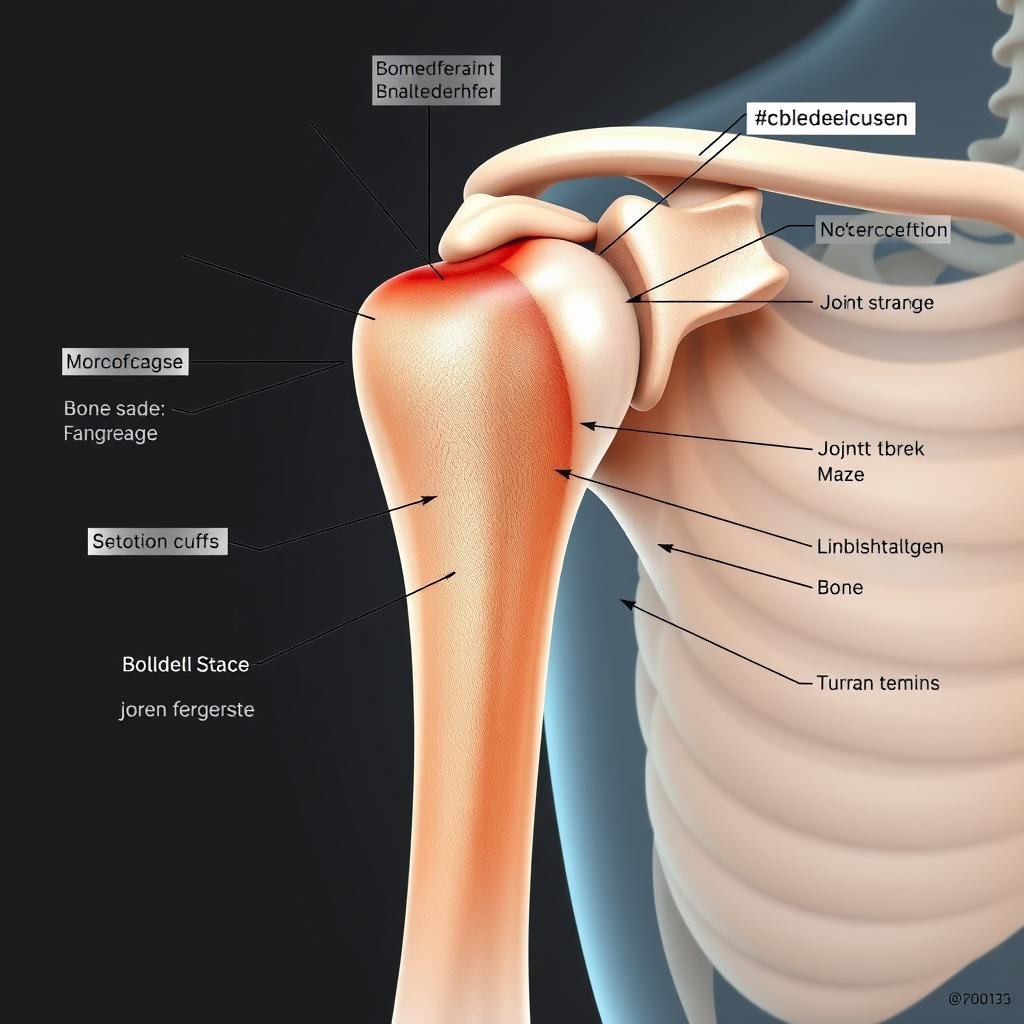

Die Schulterarthrose (Omarthrose) kann den Alltag erheblich einschränken. Wenn konservative Therapien und herkömmliche Operationen keine Linderung mehr bringen, kann eine inverse Schulterprothese die Lösung sein. Besonders bei Patienten mit geschädigter Rotatorenmanschette bietet diese spezielle Form des Gelenkersatzes neue Hoffnung auf Schmerzfreiheit und verbesserte Beweglichkeit.

Die inverse Schulterprothese wurde speziell für Patienten entwickelt, bei denen neben der Arthrose auch eine Schädigung der Rotatorenmanschette vorliegt. Die Rotatorenmanschette besteht aus Muskeln und Sehnen, die das Schultergelenk stabilisieren und Bewegungen ermöglichen.

- Arthrose mit defekter Rotatorenmanschette (Defektarthropathie)

- Schulterinstabilität durch chronische Sehnenschäden

Bei Arthrose mit geschädigter Rotatorenmanschette ist die inverse Prothese besonders geeignet.